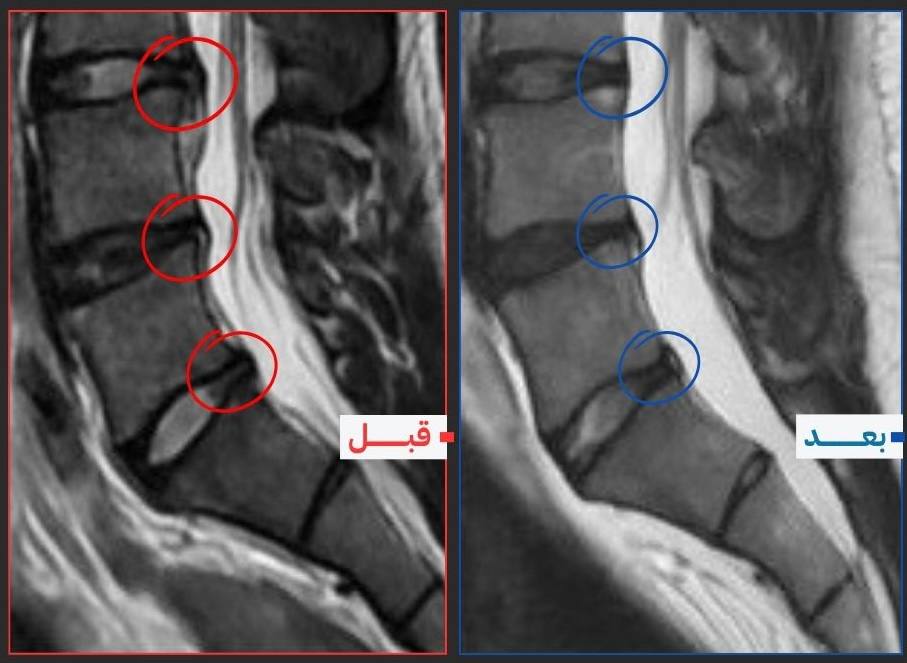

تخلص من الم الانزلاق الغضروفي و عرق النسا في ست اسابيع ب199ج فقط

دليل علمي متكامل يأخذك خطوة بخطوة لتفهم سبب الألم، تتخلص منه، وتمنع رجوعه — بدون عيادات، بدون حقن، بدون أدوية.